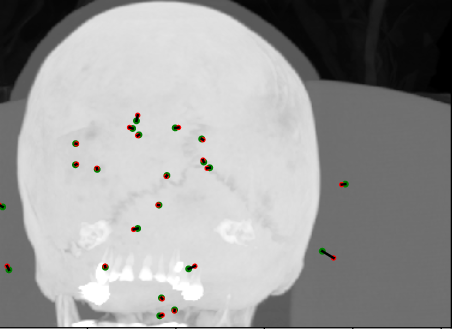

Summary metrics are shown in Table 1 for landmark localisation errors (or disagreements), and some visual results are shown for the FCN in Figures 4 and 5. The summary metrics show that the FCN outperforms the decision forest methods. The anomalous metric is the mean max error, in other words, the mean size of the “worst detected landmark in a scan”. This does not appear to improve in the second pass — if anything, the worst error worsens— and the Pass 0 decision forest with HOG features is the best performer. We propose that this occurs because landmarks with atypical appearance (e.g. see the calcified pineal gland example in Figure 5) are best located by use of spatial context rather than local appearance, hence the efficacy of low resolution HOG features which are aggregated over regions and thus are relatively insensitive to precise changes.

Figure 4: Coronal, sagittal and axial maximum intensity projections (MIPs) of results for a good case (top) and a poor case (bottom). Green dots = ground truth (observer A), red dots = detected (proposed FCN), and black lines connect corresponding pairs.